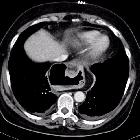

Postoperative

herniation of Nissen fundoplication. Retrocardiac air-filled structure completely surrounding the distal oesophagus.